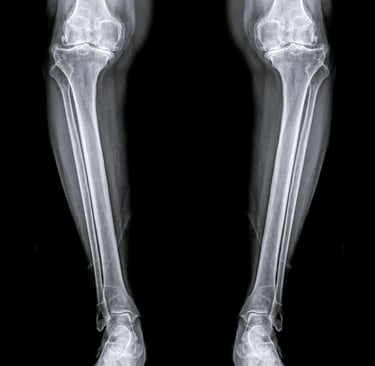

Diz kireçlenmesi, tıbbi adıyla osteoartrit, özellikle 50 yaş üstü bireylerde hareket kısıtlılığının ve kronik ağrının en büyük nedenlerinden biridir. Dizdeki kıkırdak dokusunun zamanla aşınmasıyla ortaya çıkan bu durum, "yaşlılık hastalığı" olarak bilinse de günümüzde yanlış beslenme ve hareketsizlik nedeniyle daha erken yaşlarda da görülmektedir.

Peki, her diz kireçlenmesi mutlaka protez ameliyatı ile mi sonuçlanmalıdır? Hayır. Günümüzde cerrahiye gerek kalmadan diz sağlığını koruyan ve ağrıları dindiren pek çok yenilikçi yöntem mevcuttur.